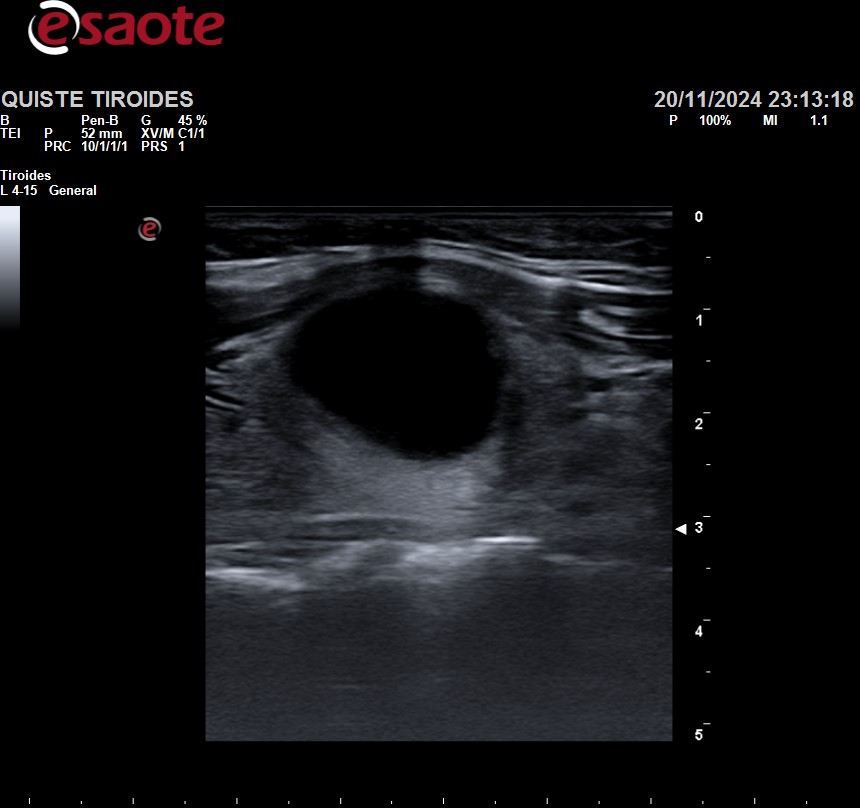

Ante dichos hallazgos, se realiza ecografía clínica tiroidea, observándose lóbulo tiroideo izquierdo sin alteraciones, y en lóbulo tiroideo derecho se observa una lesión anecoica de paredes lisas, con mínimo contenido en su interior heterogéneo, sin captación de Doppler, de unos 3cm de diámetro. No se visualizan adenopatías circundantes.

Al tratarse de un nódulo tiroideo TIRADS 1, de características benignas, y con análisis anodinos, fue dada de alta con cita en consultas de Endocrinología, para realizar seguimiento y valorar si fuera necesario drenaje del quiste.